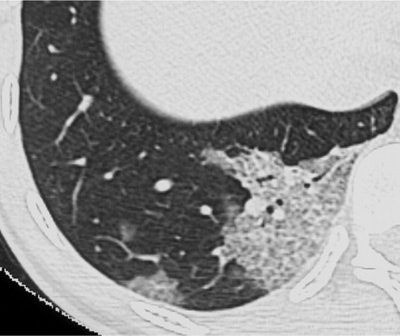

| Transverse thin-section CT scan of right lower lobe in a 25-year-old woman with SARS (obtained at day 3 after admission) shows two areas of ground-glass opacification, with thickened interlobular septa giving crazy-paving appearance. Images and caption from Radiology Online, June 12, 2003, republished by permission of the author and the Radiological Society of North America, © RSNA 2003. |